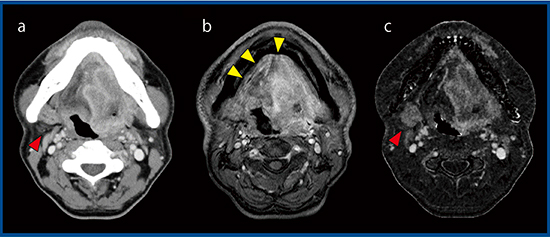

症例2は,61歳,男性の右舌縁がんである(図2)。インプラントがあるため,金属アーチファクト低減(Metal Artifact Reduction:MAR)技術の“SEMAR”(Single Energy Metal Artifact Reduction)を適用し,さらに,SURESubtractionを用いることで,腫瘍の範囲を同定できた(図2 c◀)。また,症例3は50歳,男性の舌がんである(図3)。造影MR画像では,撮像時間が長いためにモーションアーチファクトが発生し,腫瘍の同定が困難である(図3 b)。一方,SURESubtractionでは,腫瘍の辺縁も明瞭に描出され,リンパ節転移も観察できる(図3 c▶)。

図3 症例3:舌がん

a:造影CT画像 b:造影MR画像 c:SURESubtraction